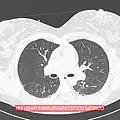

El TAC mejora el contraste de la radiología convencional, tal y como se ve en las siguientes imágenes.

La tomografía computarizada (TC), denominada en sus comienzos como TAC (Tomografía Axial Computarizada), es una técnica de imágenes digitales que ha tenido un gran impacto en el desarrollo de la medicina actual. Se basa en el uso de un haz de rayos X muy colimado, donde la radiación trasmitida a través de un objeto —en medicina, el paciente recostado en una mesa radiológica— es medida por un conjunto de detectores ubicados en oposición a la fuente de rayos X. Luego de múltiples mediciones realizadas alrededor del objeto, la respuesta eléctrica del set de detectores es enviada a un ordenador, el que mediante algoritmos computacionales (como por ejemplo, el algoritmo de retroproyección filtrada), es capaz de construir una imagen seccional del objeto utilizando la data medida y desplegarla finalmente sobre un monitor.

Esta imagen obtenida en TC es capaz de evidenciar las diferencias en las características de atenuación de las estructuras contenidas al interior de los objetos estudiados. Estas estructuras son visualizadas en el monitor con base en tonalidades de grises, las que se relacionan con un valor numérico denominado Unidad Hounsfield, asignado a cada pixel de la imagen. Este valor es calculado a partir del coeficiente de atenuación de cada material contenido en el objeto, comparado con el coeficiente del agua, usado como material de referencia. Esto mejora enormemente la resolución de contraste de la TC en comparación con la radiografía simple y la tomografía lineal. Además, mediante filtros de convolución aplicados durante el proceso de construcción de la imagen, se puede mejorar, por ejemplo, la definición de los bordes de las estructuras o reducir la presencia de ruido en las imágenes. El posterior manejo de ancho y nivel de ventana permite manipular el despliegue final de las imágenes para poner énfasis en las estructuras que se quiere visualizar de acuerdo al diagnóstico que se busca.

Imagen de corte de tomografía computarizada de pulmones con procesamiento para realce de bordes.

Imagen de corte de tomografía computarizada de ambos pulmones sin procesamiento.